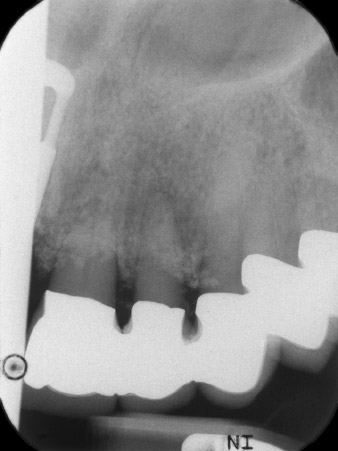

L'esito radiologico ha rivelato perdita di tessuto osseo in orizzontale attorno ai denti 21 e 22 (Fig. 1). Quando si è passati a rimuovere la corona, questi stessi denti sono stati estratti involontariamente.